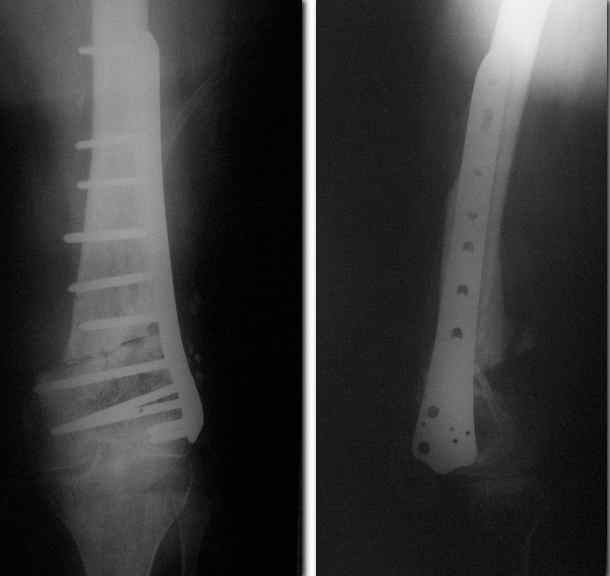

Re: Ложный сустав

послал Сергей 06 Август 2010, 17:32

Спасибо. Прооперировали во вторник.